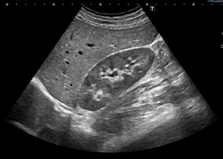

肝臓・腎臓

肝臓頚動脈腎臓